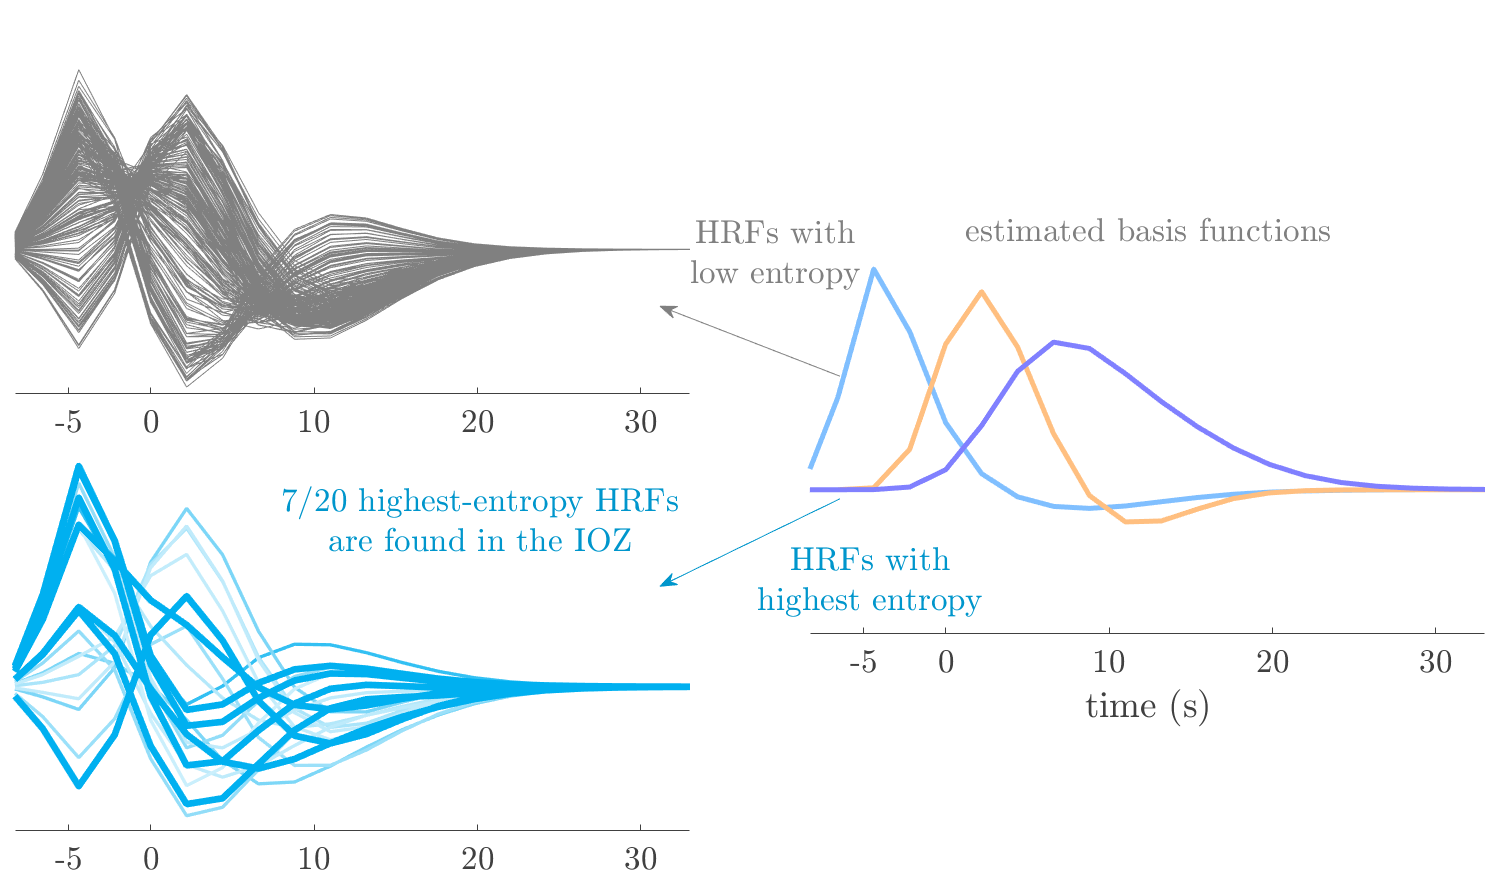

We analyze the solution with sources. Figure 1 shows the EEG signatures and HRF waveforms. One of the sources is highly correlated to the MWF reference (in grey), which was already known from Table B.3. This IED-related source had a typical low-frequency spectrum, which is expected for the typical spike-and-wave interictal discharges. The topography is relatively diffuse, although the highest amplitudes are mostly in the left hemisphere. This is in accordance with the lateralization of ictal onset zone (left temporal lobe, cfr. Table 1). There are some noteworthy observations to be made about some of the other components. The fourth has an unusually sharp spectrum, is mainly localized on two nonadjacent center electrodes, and is sustained for a single period of many seconds Hence, this component likely captured an artifact (of yet unknown origin), although we spotted no large-amplitude changes in the EEG itself. Similarly, the third source is only present at one frontal electrode, and exists in a frequency range above 20 Hz. It might represent a muscle artifact, e.g., due to frowning or twitching of some muscles in the forehead. The HRFs of all ROIs are shown in Figure 1(b). Two of the basis functions seem to have converged to a very similar waveform, which is an unfortunate possibility if two initial HRFs are too close to the same local optimum in their respective parameters. This reduces the expressive power of the basis set, which is clearly visible, since many ROIs have a nearly identical HRF. One of the twenty ROIs with the highest-entropy HRF overlapped the IOZ, although clearly this HRF (bold line) is not among the most dissimilar waveforms for this patient. This is also visible in Figure 2: both the HRF entropy and extremity maps show a small overlap with the delineated IOZ. Despite the good correspondence in the EEG domain, no significant (de)activation of the IED-component is found inside the IOZ.

We analyze the solution with sources, and show the results in Figure 3 and 4. As for patient 1, we found a source which is strongly correlated to the MWF envelope, and which had a mostly low-frequency behavior characteristic for spikes. The topography is mostly uninformative, and does not clearly correspond to the patient’s clinical data. The third source is mostly present at both sides of the head, is very sparsely active in time, and has a high-frequency content: this is most likely an artifact due to the neck muscles. Again, there is one of the highest-entropy HRFs which belongs to a ROI in the IOZ. Now, the waveform is clearly resolved from the other HRFs, through the strong initial dip (before 0 seconds). Such a dip is sometimes observed in HRFs, but its underlying physiological mechanism is not yet fully understood. It is possible that this dip reflects altered vascular autoregulation near the IOZ (cfr. the explanation in the Section 1 of the main text), or a rapid depletion in oxygen due to IED generation (before the IED becomes visible on the EEG). Figure 4 furthermore shows that the IED-related component is significantly active in parts of the IOZ, and deactive in others. As mentioned earlier, this deactivation may or may not be due to errors in sign correction. Interestingly, the ROI with the high alteration in neurovascular coupling is distinct from both the activated and deactivated ROIs.

We analyzed the solution with sources, and show the results in Figure 5 and 6. There is one source which is mostly correlated to the reference (but not extremely, see also Table B.3). This source had a right-temporal focus, conform the diagnosis in Table 1. The second source illustrates the phenomenon of an erroneous sign exchange between the spatial and spectral profiles. Also one of the HRFs has a negative polarity, which is a failure of the sign correction procedure (in this case, because there is exceptionally no positive overshoot). However, the HRF variability metrics are still interpretable, and indeed two ROIs among the ones with the highest-entropy HRFs overlap with the IOZ. The IED component is significantly active in a tiny portion of the IOZ (cfr. Figure 6). The second source is significantly active in symmetrical parts of the parietal lobe. Given its ongoing fluctuation over time, we hypothesize that this source captures a resting state network (RSN).

We analyze the solution with sources, and show the results in Figure 7 and 8. There is a clear IED-related component, with a very high correlation to the MWF reference, a typical spectrum, and an anterior-temporal focus, which corresponds very well to the patient’s diagnosis (cfr. Table 1). The fifth source seems present at only one channel, and has spectral harmonic at Hz and Hz. One of these peaks is reminiscent of the fourth component in patient 1. As Figure 8 shows, the HRF entropy and extremity prove to be strong biomarkers for the IOZ in this case, and also the significant IED activation and deactivation allow correct localization. In Figure 7, it is clear that some HRFs may still have the wrong sign, which means that the interpretation of ‘active’ and ‘deactivated’ is flipped in those ROIs. Hence, regions of significant deactivation are in fact significantly activated. The fourth source had a significant overlap with the auditory RSN, and its spectrum reveals activity in the band.

We analyze the solution with sources, and show the results in Figure 9 and 10. One source is strongly correlated to the MWF, while the other source is likely an artifact, given its very sparse temporal profile. Both sources coincide at one high-amplitude peak, by which we infer that this is probably an artifactual period in the signal. Indeed, when inspecting the original EEG signals, we found high-frequency muscle artifacts at these times. This source also had no significant activation in its spatial map, which corroborates its non-neuronal origin. The IED-related source had a broader spectrum than most other cases, and an uninformative topography. None of the ROIs with high-entropy HRFs is located in the IOZ. The pseudo t-map provides correct localization of the IOZ, however.

We analyze the solution with sources, and show the results in Figure 11 and 12. We found a clear IED-related component, with a characteristic spectrum and a topography which is backed up by the patient’s diagnosis (left anterior-temporal IOZ). The fourth source has a very similar topography and spectrum to the fifth source in patient 5. One HRF inside the IOZ had a high-entropy, and is distinguishable from the others by its very sluggish waveform, i.e., it is smeared out in time, with no sharp over- or undershoot. Also the pseudo t-map provided an accurate localization of the IOZ. Notably, in this patient, the extremity metric misses the deviating HRF in the IOZ (while the entropy metric picks it up). The second source overlapped with the frontal part of the default mode network (DMN), and is active in the and low bands.

We analyze the solution with sources, and show the results in Figure 13 and 14. We found two components which had correlated time courses. At the time of the peaks, we found higher-amplitude events in the EEG with dubious origin, hence they may or may not be artifacts. One of both components is more strongly correlated to the MWF, and its activation is concordant with the IOZ. The second component shows high overlap with the sensorimotor network. For this patient, none of the IOZ’s ROIs had extreme values of either HRF metric.

We analyze the solution with sources, and show the results in Figure 15 and 16. In this patient, there is only a moderate correlation of a component with the MWF reference time course. This component’s topography (left occipital) agrees with the clinical description, however. The HRF extremity (and not the entropy) is high in a small part of the IOZ. Both the significant IED activation and deactivation allow correct localization as well. The second source seemingly captured high-frequency oscillatory activity in the sensorimotor network, similar to the previous patient.

We analyze the solution with sources, and show the results in Figure 17 and 18. The IED-related source had a high correlation with the MWF reference, but an odd bimodal spectrum. Its EEG topography is very consistent with the clinical description. Both HRF extremity and entropy are useful biomarkers for the IOZ. The IED activation and deactivation maps each had a very small overlap with the IOZ. The second source is temporally sparse and captures high-frequency EEG variations, which we identified as muscle artifacts.

We analyze the solution with sources, and show the results in Figure 19 and 20. Again we observe an IED-related source and a seemingly artifactual source with a spectral peak near 34 Hz. Many of the high-entropy HRFs are highly noncausal, and are associated to ROIs inside the IOZ. Hence, with both HRF metrics, the highest-scoring ROIs provides good localization of the HRF. While there are no significantly active ROIs in the IOZ, there are several significantly deactivated ROIs, which may indicate that the sign standardization was not done flawlessly (cfr. also some of the negative-peaking HRFs for patient 10). Surprisingly, the second source had one significantly active ROI, which overlaps with the IOZ, but which did not match its EEG topography. Hence, the nature of this source remains ambiguous.